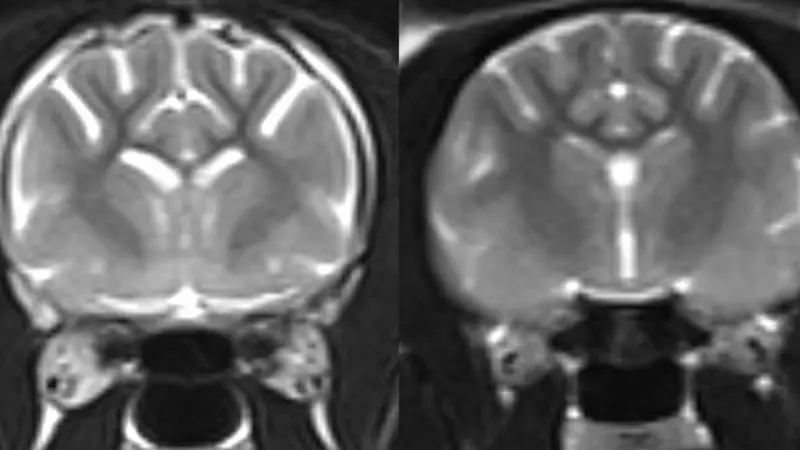

Posnetki možganov starejših mačk, ki so kazale simptome mačje demence, so razkrili, da se je amiloid-beta kopičil v sinapsah, torej stikih možganskih celic. Sinapse omogočajo pretok sporočil med možganskimi celicami, njihova izguba pa povzroča zmanjšanje spomina in miselnih sposobnostih pri ljudeh z Alzheimerjevo boleznijo.